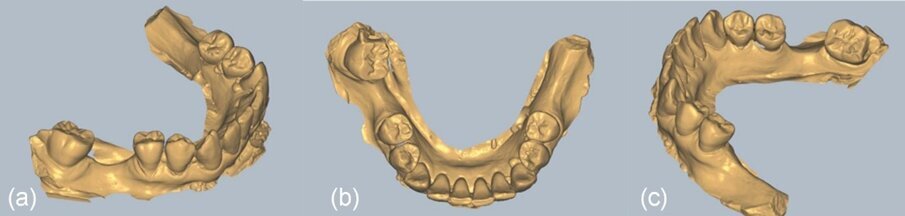

In questo caso particolare abbiamo eseguito una impronta digitale prima del trattamento chirurgico con un dispositivo di scansione intraorale e un file STL è stato inviato al tecnico di laboratorio. Lo scopo del flusso di lavoro digitale adottato qui era di progettare digitalmente e preparare l’unità di profilo personalizzato e un template come guida per il taglio della barriera lamellare con i seguenti processi:

Creazione del profile

Il file STL è stato prima importato nel software exocad (Fig. 16). Successivamente, è stata selezionata e importata nel software una tabella digitale VPI Cervico adatta al sito e allo spazio interprossimale (Fig. 17). Un’unità di profilo corrispondente all’abbinamento digitale della tabella è stata progettata dopo la scansione del modulo VPI Cervico con un dispositivo di scansione Ceramill Map 400 (Amann Girrbach) e posizionata 3 mm al di sotto della gengiva sul modello exocad. Il design è stato inviato all’operatore e, dopo la sua approvazione, è stata creata una scanalatura di 1 mm di larghezza e 0,5 mm di profondità a livello della mucosa marginale utilizzando gli strumenti di exocad (Figg. 18, 19). Il profilo è stato quindi stampato con una stampante 3D Asiga 3D max utilizzando una resina free print temp A2, pulito con alcool isopropilico al 99%, post-indurito utilizzando Otoflash G171 con azoto e infine rimosso dalla sua struttura di supporto e pulito con un vaporizzatore (Fig. 20). Questa unità di profilo è stata collegata in bocca durante l’intervento chirurgico con il cilindro temporaneo per generare un moncone personalizzato. Sono state aggiunte estensioni mesiali e distali occlusali ai denti vicini 45 e 47 all’unità al fine di facilitarne il posizionamento e l’adattamento all’interno del cilindro provvisorio.

Fig. 16_Immagini CBCT preoperatorie del sito 46.

Fig. 17_a) fino a c): Viste del file STL nel software Exocad.